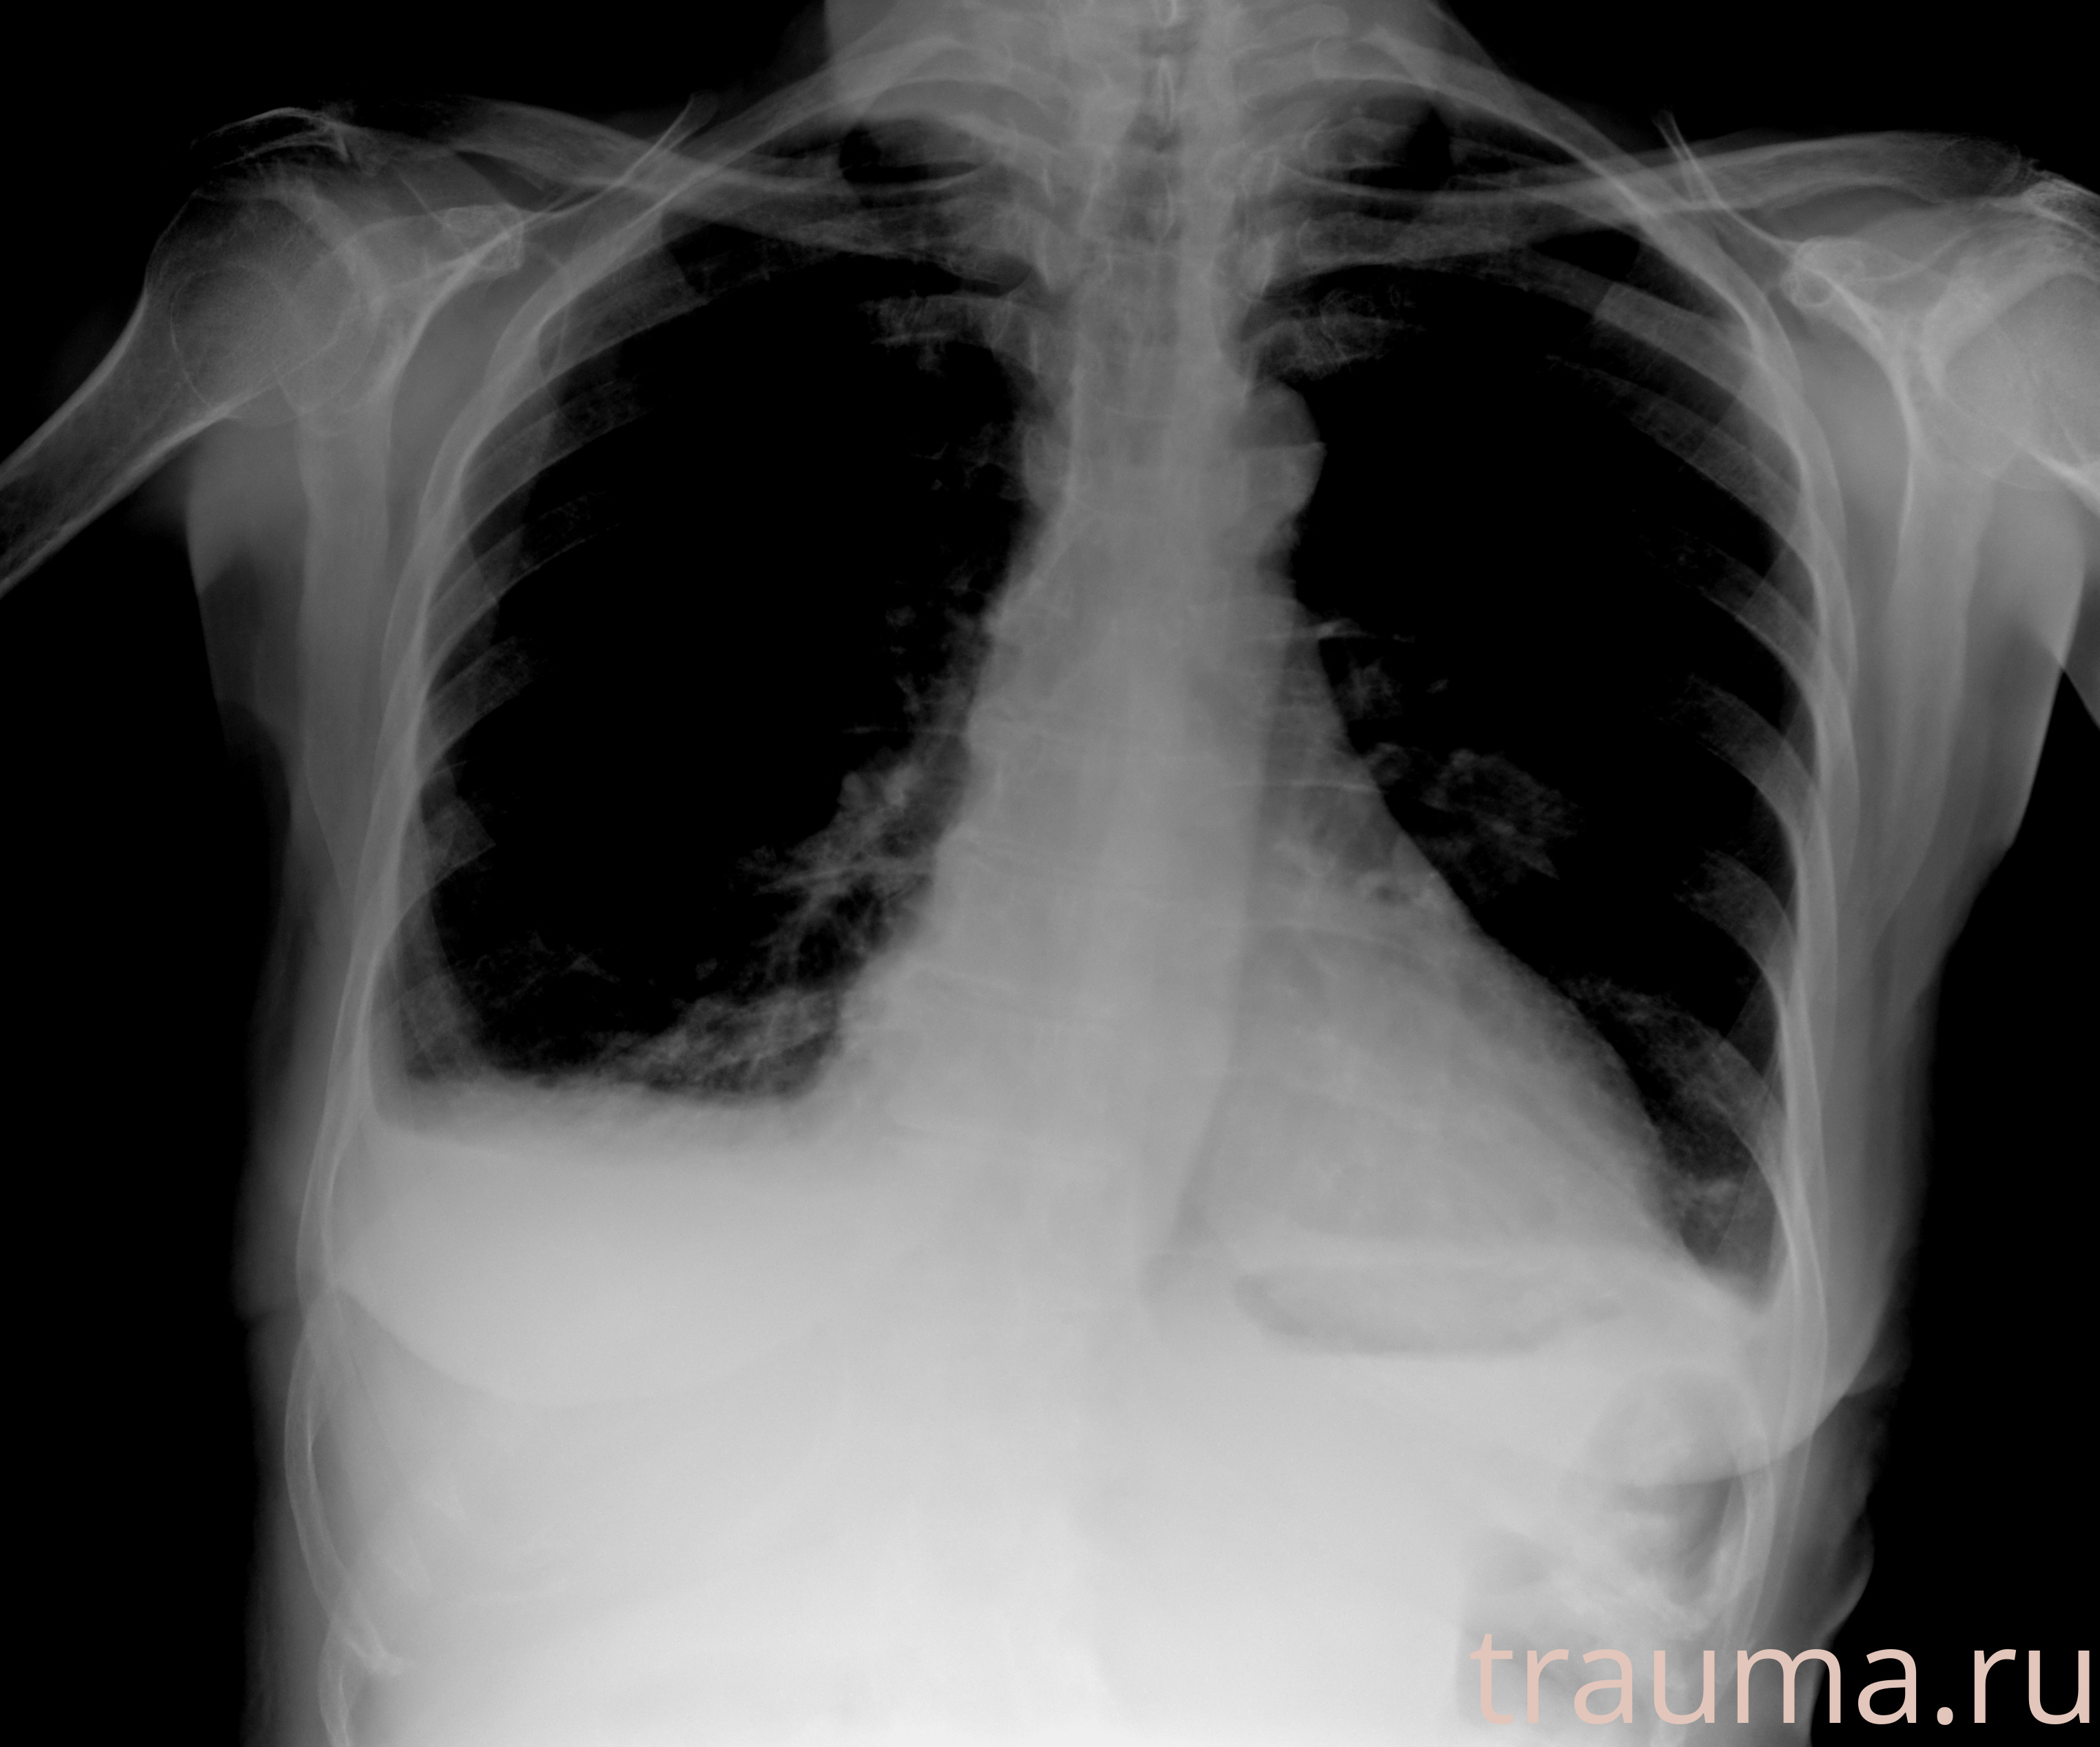

Рентгенограммы

Натуживание 26.12.2025 21:16:34

Рентген на дому: по вашему адресу приезжает врач-рентгенолог, травматолог-ортопед с мобильным рентгеновским аппаратом, проводит диагностику травмы или заболевания, делает необходимые рентгенограммы, дает рекомендации по дальнейшему лечению. Получить качественные снимки в домашних условиях возможно благодаря уникальной методике, разработанной МосРентген Центром для института  Склифосовского